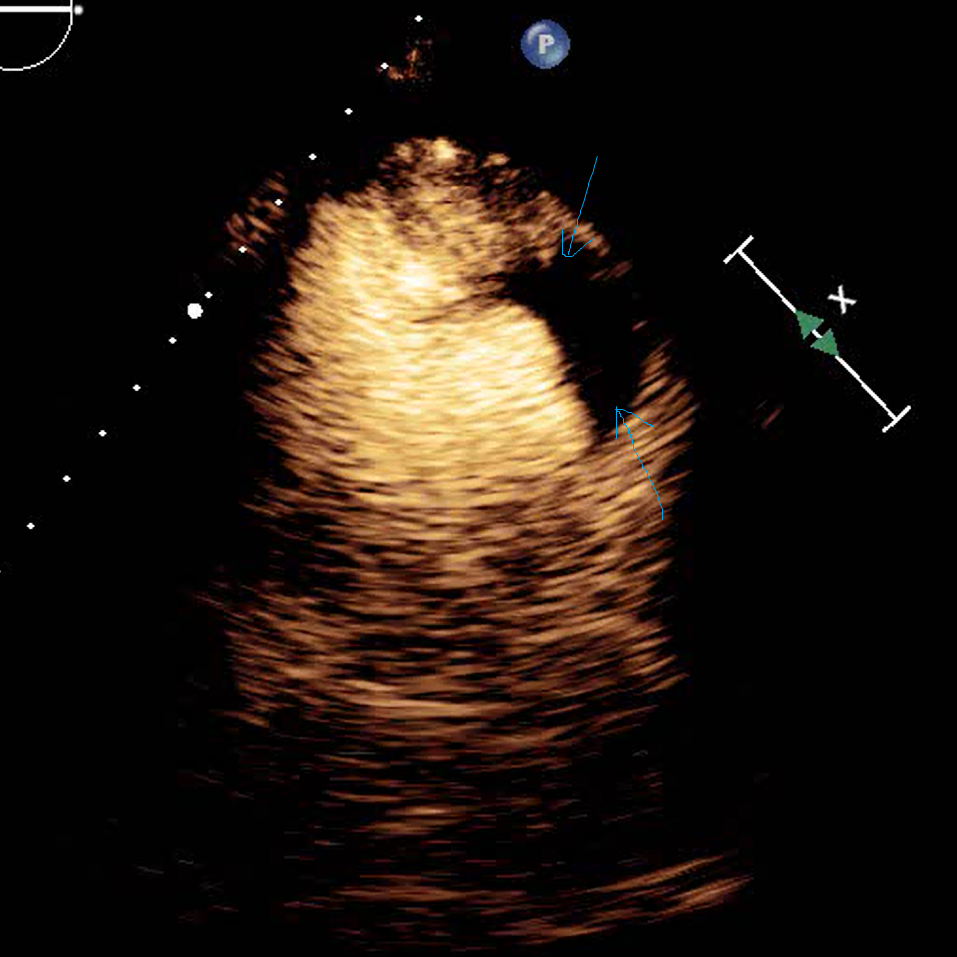

Large echolucent area (blue arrows) after contrast confirms thrombus